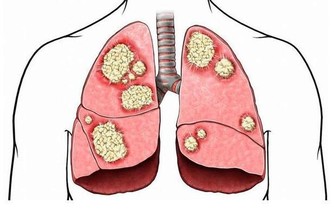

抽煙傷肺我們聽多了,為什麼也會傷肝呢?

因為香煙中的尼古丁是通過肺和肝臟代謝的,如果大量的吸煙,肝臟解毒的工作負擔會進一步加重。而且,尼古丁會使人興奮,導致血管收縮,並且增加血液粘稠度。這樣就會使肝臟的供血減少,使肝臟無法獲取營養。